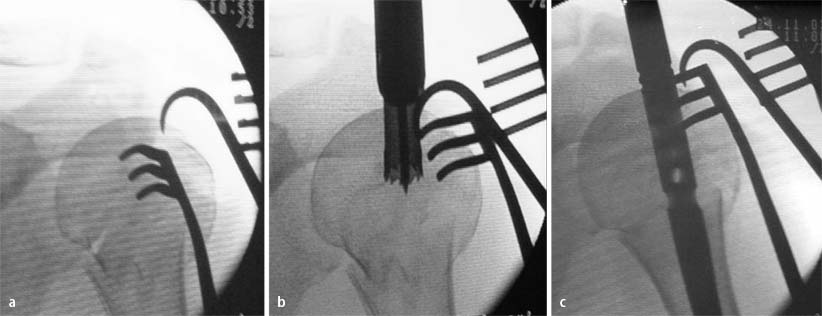

Reposition und Nageleintrittspunkt

Unter Zuhilfenahme eines Instruments wie Raspatorium, Elevatorium oder 2 gekreuzten Kirschner-Drähten als Joysticks wird das Kalottenfragment reponiert. Der ideale Nageleintrittspunkt wird am höchsten Punkt der Kalotte aufgesucht, durch einen Kirschner-Draht markiert und mit einer Hohlfräse unter Schonung der Sehnenränder überbohrt (Abb. 4). Die zirkuläre knöcherne Abstützung des proximalen Nagelendes im subkortikalen Knochen ist die wichtigste Voraussetzung für die Stabilität der Osteosynthese bei Mehrfragmentfrakturen.

a Reposition mit dem Einzinker, b Eröffnen des Nageleintrittspunkts mit der Hohlfräse, c Einführen des Nagels